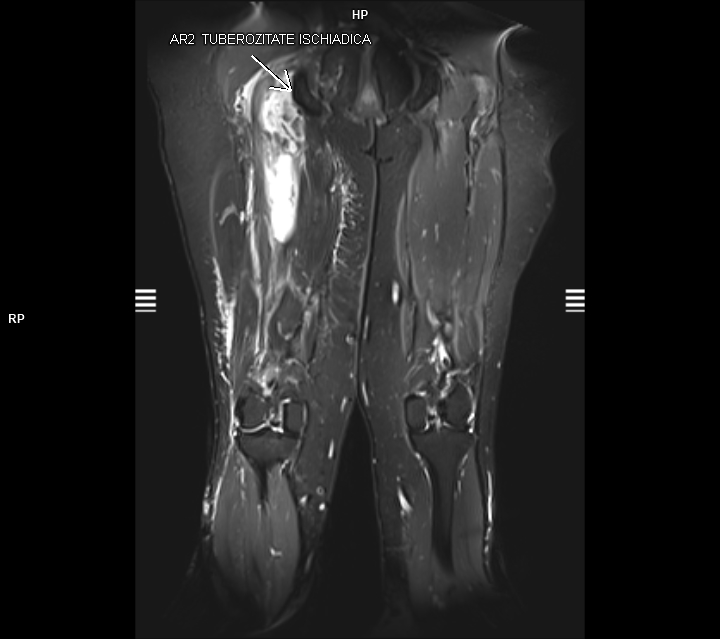

Figurile 3 si 4: coronal T2 cu saturația grăsimii coapsă bilateral

Discuţie caz nr 92: Harmstring lesion este dificil de tradus în limba română și se referă la leziunea celor trei mușchi ce se inseră pe tuberozitatea ischiadică: semitendinos, semimebranos și biceps femural. Cazul prezentat este a unui pacient care s-a aplecat la cumpărături să ridice o plasa și a simțit o durere puternică în spatele coapsei urmată de impotența funcțională si de creștere de volum a coapsei posterior. Pe imaginile postate se evidențiază avulsia tendonului comun al celor trei muschi ce se regăsește retractat inferior cu formarea unui hematom în vecinătate.